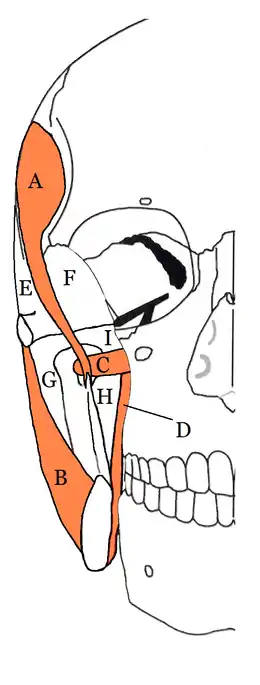

The deep temporal space is a fascial space of the head and neck (sometimes also termed fascial spaces or tissue spaces). It is a potential space in the side of the head, and is paired on either side. It is located deep to the temporalis muscle

The inferior portion of the deep temporal space is also termed the infratemporal space. The deep temporal space is one of the four compartments of the masticator space, along with the pterygomandibular space, the submasseteric space and the superficial temporal space.[1] The deep temporal space is separated from the pterygomandibular space by the lateral pterygoid muscle inferiorly and from the superficial temporal space by the temporalis muscle laterally. The deep temporal space and the superficial temporal space together make up the temporal spaces.[1][2][3][4]

The boundaries of the deep temporal space are:

Superior:

Superior and Inferior temporal lines

Inferior:

Infratemporal crest and Zygomatic arch